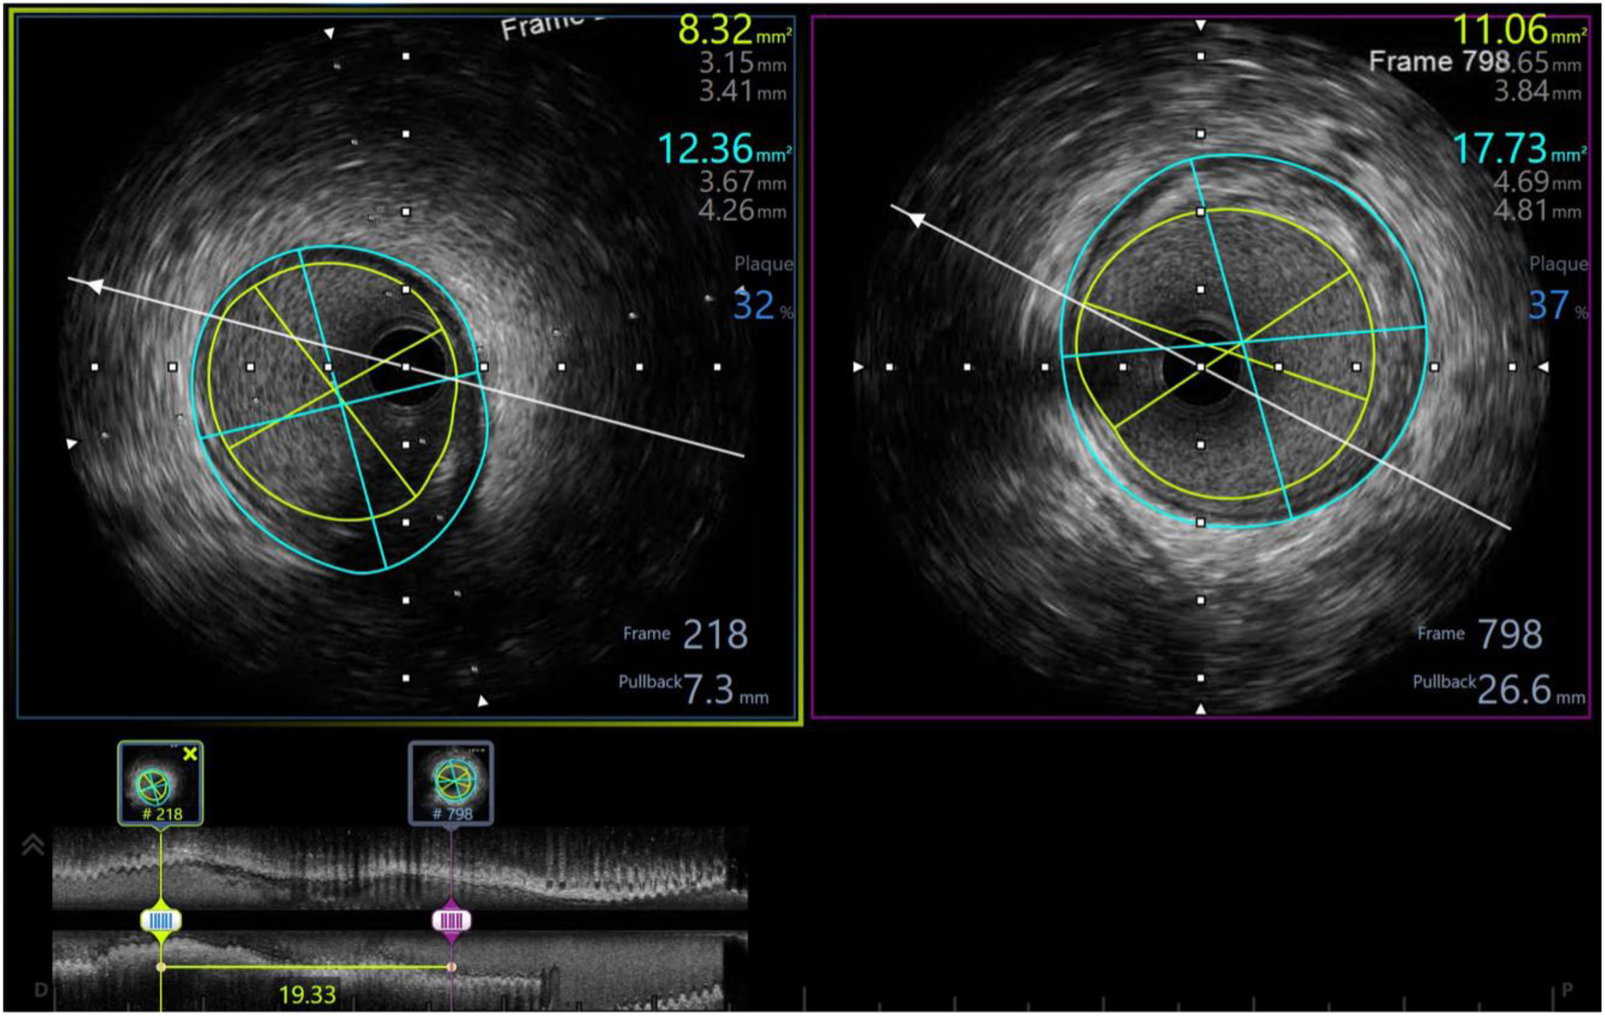

In our study, 98.3% of patients received intravascular ultrasound prior to implantation to evaluate the lesion characteristics and to select the appropriate scaffold size, as well as an intravascular ultrasound after the intervention to evaluate the effectiveness and success rate of the procedure. All of the patients received post-intervention balloon dilation. The efforts to follow the same process have helped the procedure to achieve a successful intervention rate of 100% (Table 6). Figures 3–5 displayed IVUS imaging of a patient who underwent Magmaris implantation using IVUS.

Figure 3

Pre-procedure IVUS showed distal reference: lumen diameter 3.15 × 3.41 mm, vessel diameter: 3.67 × 4.26, plaque burden: 32%; proximal reference: lumen diameter 3.65 × 3.84 mm, vessel diameter: 4.69 × 4.81, plaque burden: 37%; lesion length: 19 mm.